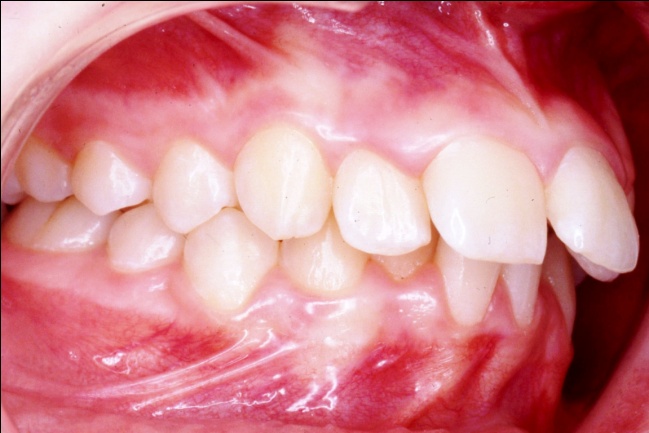

3 - L’art du contrôle en orthodontie

Le traitement a reposé sur des extractions ciblées et une mécanique orthodontique complexe, utilisant la méthode de Tweed avec ancrage maximal pour reculer les dents antérieures sans avancer les dents postérieures. Cette rétraction des blocs incisivo-canins a permis de repositionner les lèvres et d’harmoniser le profil. Un tel contrôle des mouvements dentaires est impossible avec de simples gouttières d’alignement, qui ignorent l’impact sur les tissus mous.